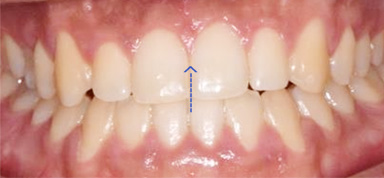

주걱턱으로 앞니가 서로 거꾸로 물리고 어금니가 제대로 물리지 않는 남환, 타 병원에서 양악 수술 진단을 받고 내원하셨습니다.

고운미소에서 교정용 미니스크류를 이용하여 아래 치열은 후방이동, 위 치열은 전방으로 이동하는 치료를 진행하였습니다.

위턱에 비해 아래턱이 크고 전방에 위치, 우측으로 변위된 비대칭을 보입니다.

비 수술교정치료 이후 제대로 물리지 않던 어금니와 앞니 배열이 정상적으로 돌아왔습니다.